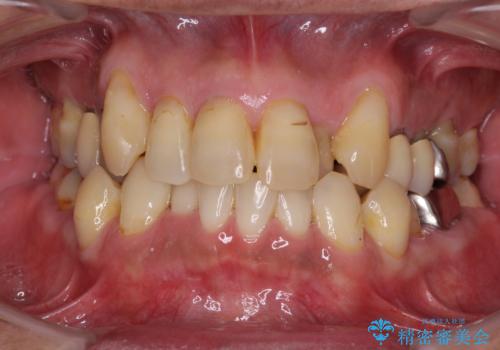

![[MTMを行い歯の神経を保存] 歯周補綴ブリッジの症例 治療前](https://seimitsushinbi.jp/wp/wp-content/uploads/2021/04/21310c2f37874ac2f2ba9939da2fee68-500x350.jpg?v=1618452125)